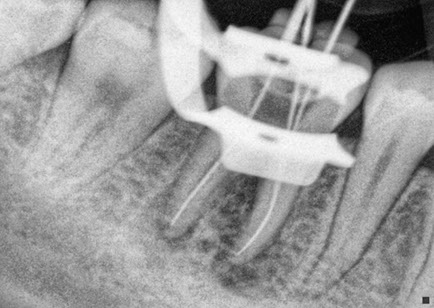

La endodoncia le da más tiempo de vida útil a su pieza dental, en Dental Evolution Cancún le recomendamos evitar la extracción realizándose este procedimiento que garantizamos será sin dolor, gracias a la tecnología de vanguardia con la que contamos, instrumental rotatorio, sistema de ultrasonido, y a nuestra “radiografía digital” la cual juega un papel crucial en el procedimiento de endodoncia, además de que usted estará atendido con la calidez, calidad humana y  profesionalismo que caracteriza a nuestro experto equipo de dentistas  especializados que le apoyaran en todo momento.